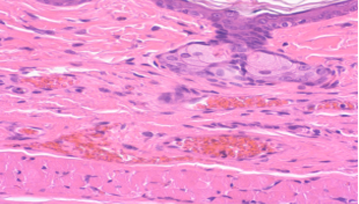

拥有屏障环境和普通环境的动物设施,建立实验动物临床病理和组织病理学实验室,具有丰富毒理学研究和GLP经验的技术团队,配备各领域专业团队,可提供技术服务可进行兔、豚鼠、地鼠、大鼠、小鼠等动物试验。

实验室团队具备丰富的动物毒理学研究经验和专业的技术能力。可提供食品、保健食品、药品、化妆品、消毒产品、医疗器械等领域的检测服务。